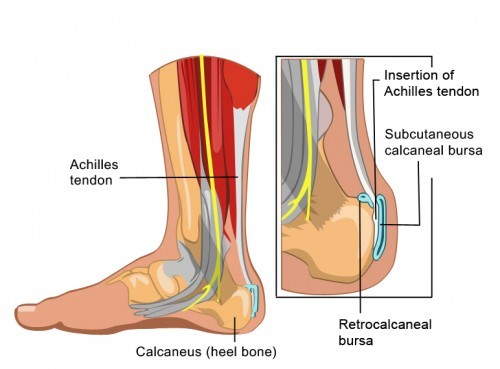

Bursitis and Tendonitis

Bursitis is an inflammation of a bursa sac. Bursa sacs are located between bone and skin. They allow the skin to slide over bony prominences in the body, such as the knee, shoulder, and elbow. When a bursa sac becomes irritated and inflamed, it causes pain and discomfort in the nearby joints. Tendonitis is an inflammation or irritation of a tendon.